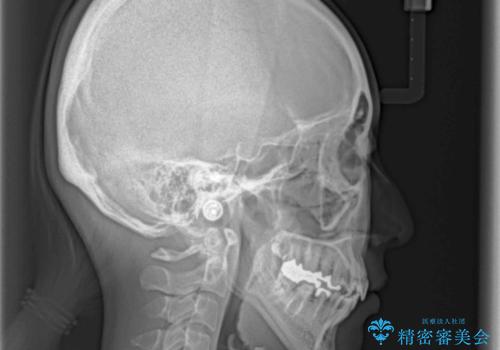

上顎骨拡大を併用したインビザライン矯正

上下の骨幅を改善したことで、スムーズに歯列矯正を行うことができました。

矯正治療中に近医で銀歯を外す治療を開始したため、治療後に奥歯の咬み合わせが不十分ですが(こちらは近医での治療により改善するとのこと)、歯列と咬み合わせが改善され、患者様には大変満足していただきました。